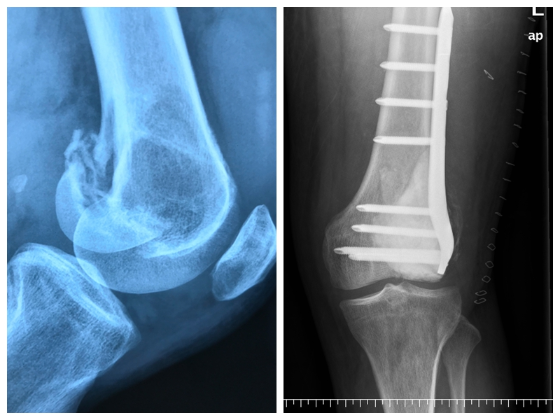

经过一系列检查和病理活检,医生认为他左侧股骨外髁可能长了骨巨细胞瘤,同时出现了病理性骨折,建议他做手术,换成人工关节——“人工肿瘤铰链膝关节”。 然而人工关节费用价格不菲,整个治疗费用将近10万元,家庭经济困难的何先生犹豫不决。

经朋友介绍,何先生找到了南方医科大学第五附属医院关节外科主任潘乘龙。检查显示,何先生的外髁骨已经是粉碎骨折,骨折移位明显,骨量被肿瘤侵蚀得所剩无几。

5月15日,手术正式进行,潘乘龙主刀。在手术中,医生们看到,何先生的左股骨外髁内布满了肿瘤组织,当即取出部分肿瘤组织制成冰冻切片送病理科检查。十几分钟后,报告结果出来,何先生的骨巨细胞瘤是良性的!

“这个消息让我们顿时松了一口气。”潘乘龙说。手术继续进行。潘乘龙观察到,何先生的膝关节仅剩下了骨皮质及软骨层,骨头如薄片,十分脆弱,怪不得无法支撑他正常行走。

经全方位反复刮除及灭活肿瘤组织后,潘乘龙小心翼翼地将骨折端复位,并取下患者自身的骨组织填充。当关节面、骨折端复位好后,再拧入钢板螺钉,最后注入骨水泥填充骨缺损处,手术顺利完成。

术后第二天,何先生即可拄拐下地负重步行。经过农村合作医疗报销后,他自己只需支付2.5万元左右。术后复查发现,他的骨折复位良好,关节面平整。半个月后,他就可以出院回家疗养了!